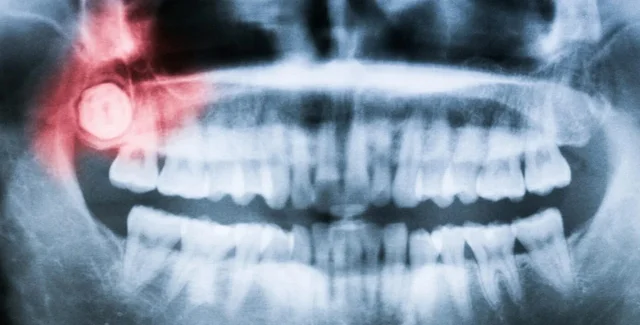

Фото: popsci.com

Большинство людей не помнят, как у них начали появляться первые зубы, но многие помнят, как прорезывались зубы мудрости и, конечно же о то, как их удаляли. В новом исследовании ученые предлагают свою версию того, почему зубы мудрости появляются так поздно, сообщает popsci.com

По словам ученых, причиной позднего роста зубов мудрости может быть медленное развитие наших челюстей.

"Наши челюсти растут очень медленно, вероятно, из-за нашей относительно большой продолжительности жизни и, в сочетании с нашими небольшими лицами, зубы мудрости не растут пока не будет необходимого безопасного пространства", — говорит Гэри Шварц, палеоантрополог из Университете штата Аризона.

Фото: pexels.com

Наши зубы подвергаются значительному механическому давлению во время пережевывания пищи, как и вся структура челюсти. А это означает, что челюсть должна быть готова к развитию, чтобы зубы располагались по всей глубине рта, ближе всего к челюстному суставу. Если бы зубы мудрости появились раньше, они могли бы повредить челюсть, из которой выросли, говорит ученый.

Сочетание этих факторов означает, что наши челюсти не могут приспособиться к последнему набору коренных зубов до взрослого возраста.

"Многим людям удаляют зубы мудрости, потому что некоторые считают их пережитком эволюции, который больше не нужен. Но их не обязательно удалять. Это нужно делать только в том случае, если они вызывают проблемы", — говорит Гэри Шварц.